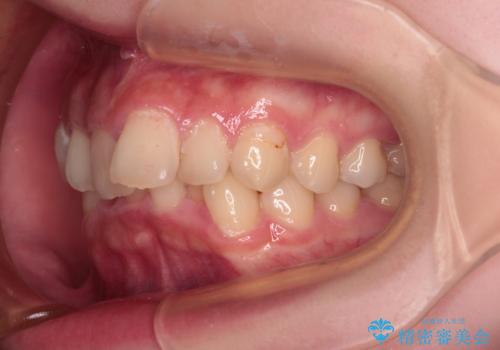

【モニター】デコボコと隠れてしまう前歯 ワイヤー装置による抜歯矯正で美しい口元に

- デコボコになっている前歯を気にして来院された患者様です。

口元の突出感は気になっていないものの、デコボコを解消すると口元が前方に突出する可能性があるため、上下左右の第一小臼歯4本を抜歯して、ワイヤー装置にて矯正治療を行うこととしました。

下の前歯が隠れてしまうほど深く咬みこんでいたため、上顎前歯が前方に突出しているような印象がありましたが、咬み合わせが改善され、整った口元に仕上げることができました。